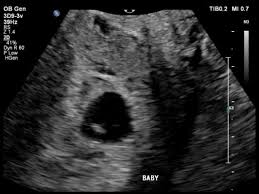

I was scared and anxious that my baby may stop growing any moment. 9 weeks pregnant and measuring small slow growth of baby. IUGR is usually diagnosed after an ultrasound shows your babys weight is below the 10 th percentile based on how many weeks pregnant you are.

They asked me to return for another scan. Had a scan last week at 38 weeks to check for breech shes not but that scan shows shes in the 15th percentile now and Babys head and chest are measuring. Gestational Sac Measuring Small at 8 Week Ultrasound.

Baby measuring a bit small at 28 weeks. Baby Growth Behind at 8 Weeks Ultrasound - posted in PG after IVF. If theres a heartbeat at 9 weeks the probability of a miscarriage plummets and shell have greater reassurance that her pregnancy will continue.

This type of scan is called a growth scan. Its a more accurate way of measuring your babys.